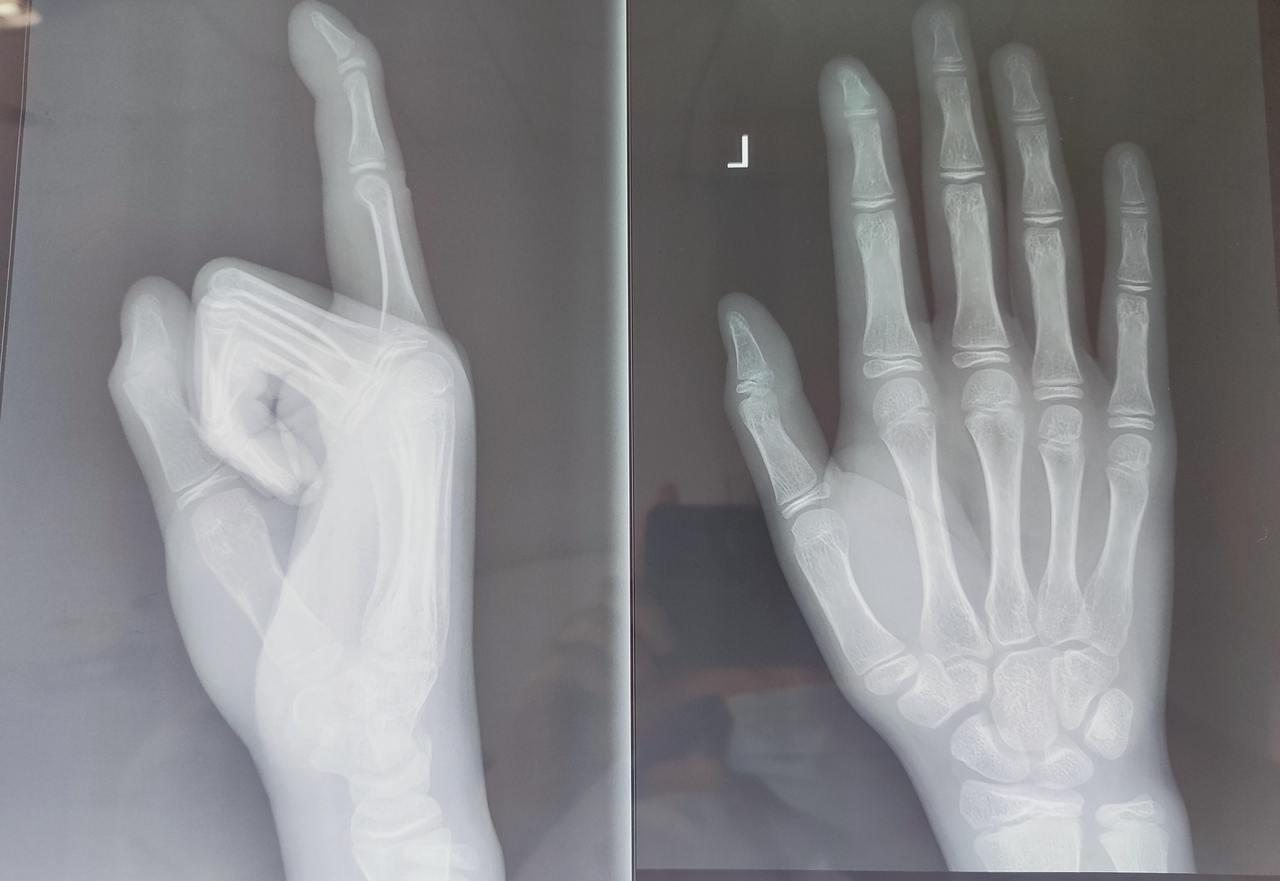

伤科门诊副主任中医师倪慧英接诊后,发现小徐是典型的锤状指。

所谓锤状指,由末节指骨基底背侧至中央腱束止点间指伸肌腱断裂或撕脱部分指骨所致,手指远节因伸肌腱损伤导致无法主动伸直,继而呈现“锤子”样弯曲畸形。“该病多见于运动损伤、撞击伤或日常磕碰。”倪慧英提醒,若处理不当,则可造成“鹅颈”畸形,影响手指外形及功能。之后,倪慧英予以手法整复及夹板外固定治疗。